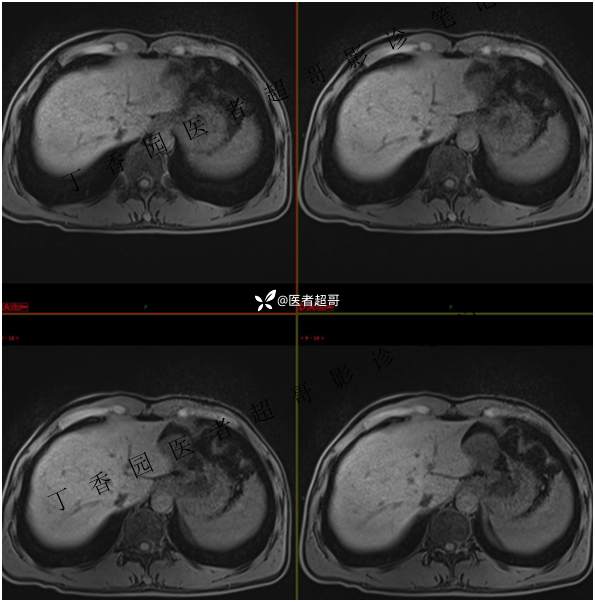

肝胃间隙肿瘤,间质瘤?平滑肌瘤?还是鞘瘤?有结果,请分析!

现病史:患者于3天前查体行肝胆脾胰肾彩超示肝内实性占位,无恶心、呕吐,无发热、寒战,无腹胀、腹泻,进一步于医院行上腹部CT增强示:肝胃交界处肿块。未行特殊治疗。今患者为求进一步治疗,来我院就诊,门诊以“肝占位性病变”收入院。患者自发病以来,神志清,精神可,饮食睡眠可,二便可,体重近期未见明显变化。